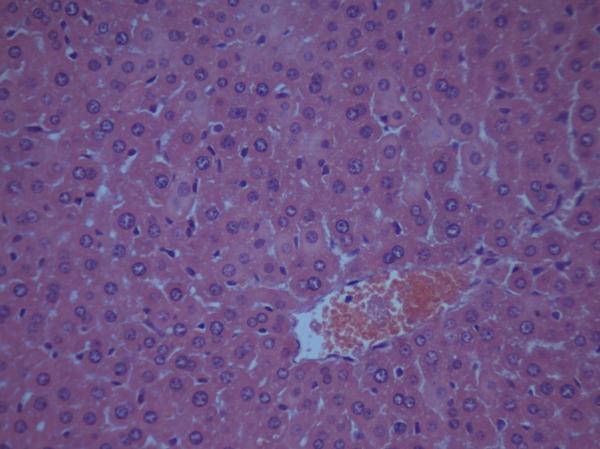

Çó¸ßÈ˰ïæ¿´Ð¡Êó¸ÎÔàÇÐÆ¬